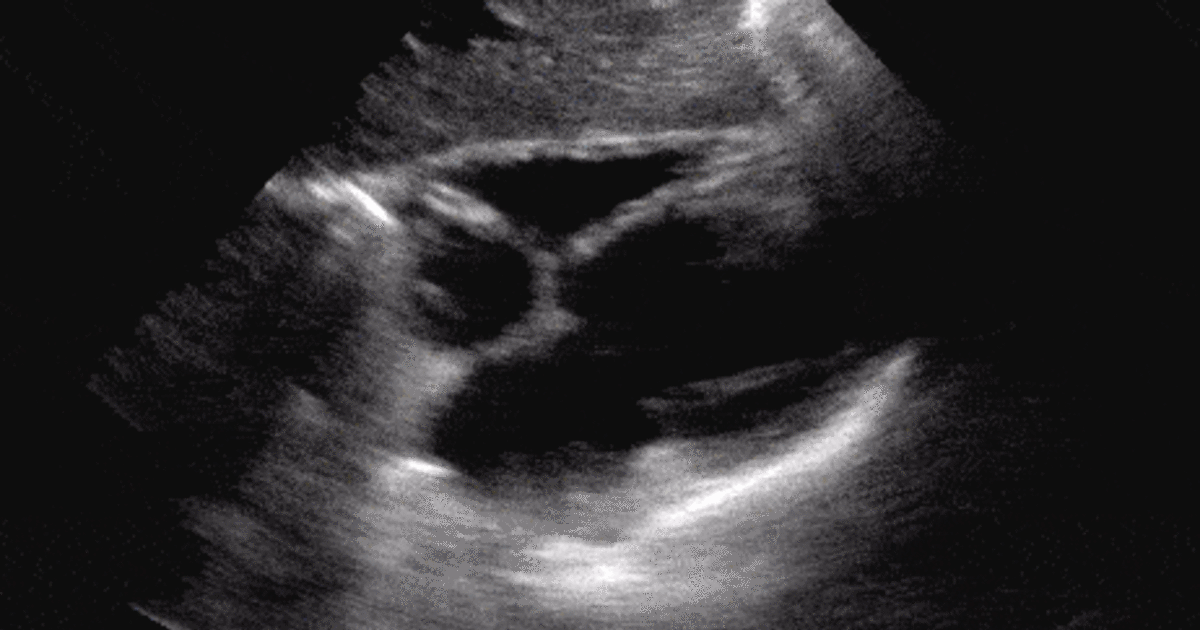

Ultrasound Case 013 • LITFL • POCUS SelfAssessment Quiz

Ultrasound Images Quiz It was created by member hannah christenberry and has 18 questions. Study with quizlet and memorize flashcards containing terms like liver,. This is an online quiz called label vessels in the ultrasound image. Explore quizzes and practice tests. They’re just for fun, but are a great way to see where you stand. Quiz yourself with questions and answers for ultrasound basics quiz, so you can be ready for test day. This online quiz is called labeling ultrasound image. This online quiz is called ultrasound image practice. Sonoquizzes are a quick and easy way to test your ultrasound knowledge! You can use it as. Test your knowledge on this science quiz and compare your score to others. What plane, and what structures are located at the corticomedullary junction? It was created by member hannah christenberry and has 18 questions. Can you label the vessels in this ultrasound image? It was created by member carly cristello and has 11 questions. 112 rows litfl 100+ ultrasound quiz clinical cases and self assessment problems from the ultrasound library to enhance interpretation skills through ultrasound problems.

From litfl.com